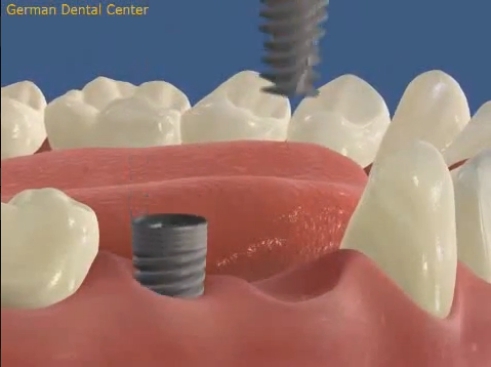

- Имплантация